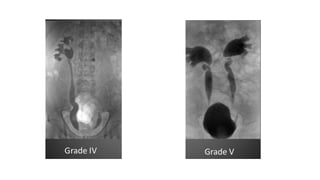

• #39 Retrograde Urethrogram showing extravastion of contarst at the site of posterior uretrhal injury